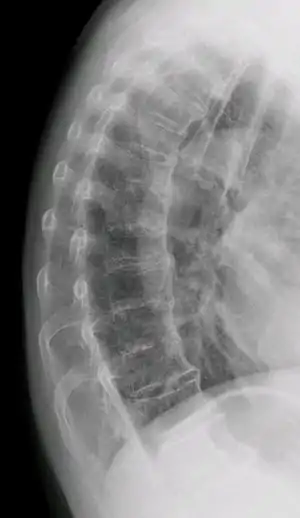

| DISH in an 80 year old female, also with T11 fracture. | |

Confluent ossification of multiple contiguous vertebral bodies in diffuse idiopathic skeletal hyperostosis (DISH)

"Melted candle wax" appearance of calcification and ossification in diffuse idiopathic skeletal hyperostosis (DISH). Note the preponderance on the patient's left side (right side of image).